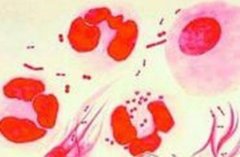

淋病是以泌尿生殖系统化脓性感染为主要表现的性传播疾病。其发病率居我国性传播疾病第二位。淋球菌为革兰阴性双球菌,离开人体不易生存,一般消毒剂容易将其杀灭。淋病多发生于性活跃的青年男女。近年来世界淋病有明显增加的趋势。我国自1975年以后,淋病又死灰复燃,病人逐年呈直线增多,是性病主要发病病种。(赵熙熙)